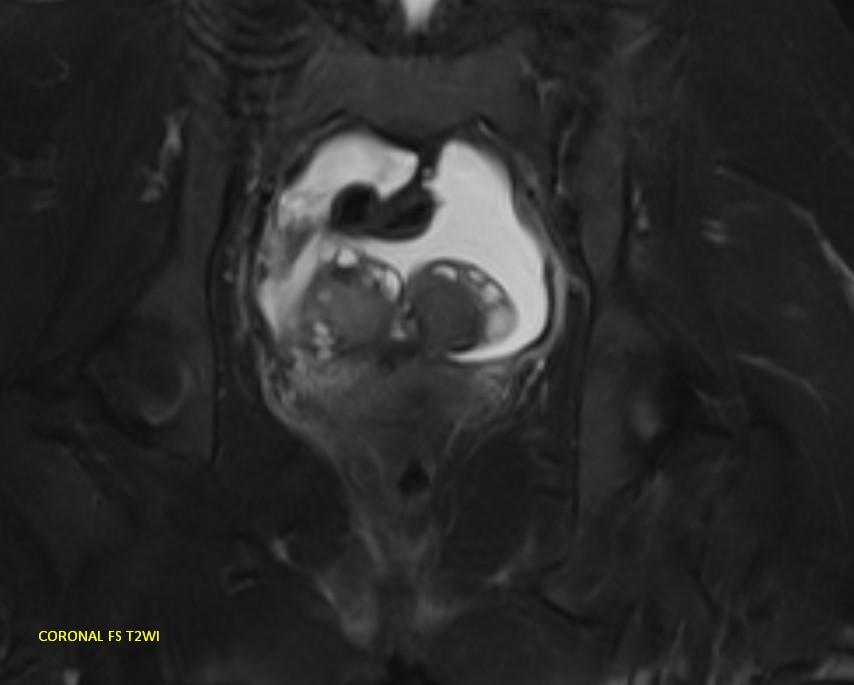

*23-year-old female with primary infertility.

Answer: Kissing Ovary Sign

MR images demonstrating the kissing ovaries, bilateral endometriomas (chocolate cysts), and peritoneal inclusion cyst (peritoneal pseudocyst).

Blood products in ovaries may cause adhesions to pull the ovaries toward the midline. This is considered a sign of pelvic endometriosis (1).